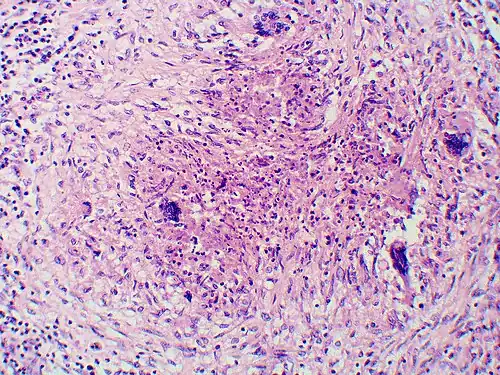

Granuloma with early suppuration. The fungal organisms are difficult to recognize at this low magnification. -

Large yeast-like fungi seen within giant cells at arrows. -

Large yeast-like fungi seen within giant cells at arrows. Budding yeasts in the cytoplasm of giant cells at the arrows. Broad-based budding and double-contoured cell walls are seen in the giant cell in the center are characteristic of Blastomyces dermatitidis. -